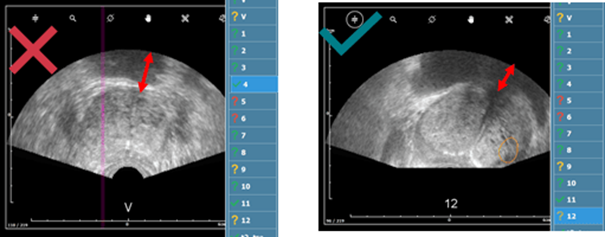

c. Pression de la sonde et défauts de sonde

- Les lobes dépassent l'image échographique → Déformation de la glande due à une pression excessive sur la prostate.

- La prostate doit être clairement visible, aucune ligne noire continue ne doit apparaitre. Si vous suspectez une image de mauvaise qualité, se rapporter à cet article.